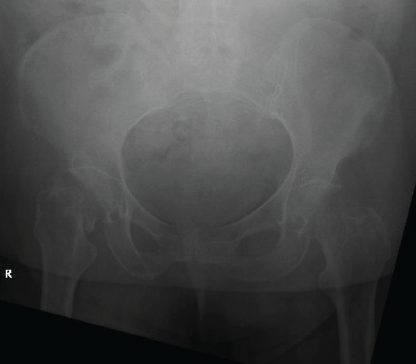

A 65-year-old female with a history of non-alcoholic steatohepatitis (NASH), stroke, pancytopenia, hypertension, aortic stenosis, uncontrolled type 2 diabetes, and obesity was brought to the emergency department (ED) after a fall onto her right hip. She was independent but used a walker at baseline. She sustained a right femoral neck fracture (Fig. 1). The orthopedics team recommended a right hip hemiarthroplasty due to the patient’s underlying medical conditions.

Figure 1: Anterior-posterior X-ray of right femoral neck fracture.